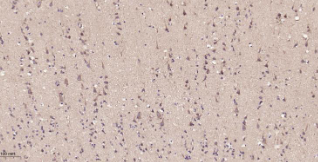

Immunohistochemical analysis of paraffin embedded Human brain tissue slide using IHC0569H (Human LRP1 Kit).